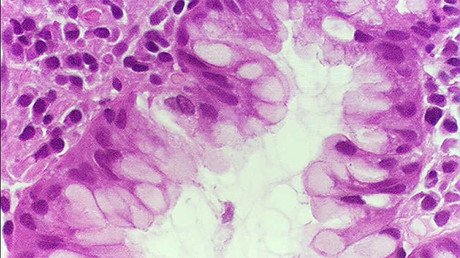

El primer caso ha sido registrado en Dinamarca, donde recientemente han hospitalizado a un paciente. Los análisis han revelado que la bacteria que afectó al ciudadano danés es una nueva versión mortífera de las bacterias del tipo 'Escherichia coli', que contienen un gen mutado conocido como MCR-1 y es resistente a los antibióticos más potentes, incluso a la colistina.